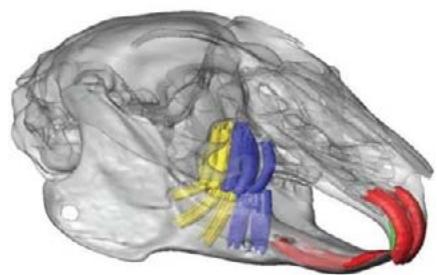

A dentição dos coelhos é o tipo heterodonte, todos os dentes são elodontes (crescem por toda a vida) o número de dentes é 28 e tem fórmula dentária: I2/1, C0/0, P3/2, M3/3. O músculomasseter é o principal músculo da mastigação; o músculo temporal é pequeno; portanto, o processo coronoide é pequeno; o crânio é fenestrado; existem grandes processos semelhantes a asas nos ossos frontais; há um grande forame incisivo; há uma ponte palatina entre os pré- molares formados por porções dos ossos maxilar e palatino; possuem grandes bolhas timpânicas EMILY, Peter (2021). A mandíbula superior do coelho contém três pré-molares e três molares, enquanto a mandíbula inferior possui dois pré-molares e três molares através da visualização das raízes dosdentes a partir dos dados de micro tomografia computadorizada observou-se que os pré-molares da mandíbula têm raízes predominantemente orientadas verticalmente (Fig. 1). Em comparação, enquanto as raízes molares na maxila também são verticais, elas têm uma orientação mais posterolateral na mandíbula. WATSON, Peter J. (2014). A altura média da coroa dos incisivos mandibulares e maxilares em coelhos domésticos adultos é de 6,0 mm. A profundidade de sondagem periodontal saudável normal dos incisivos inferiores em coelhos é de 5 a 6 mm. Os pré-molares e molares são agrupados como uma unidade funcional com uma superfície oclusal relativamente horizontal com dobras transversais de esmalte para triturar e picar alimentos fibrosos difíceis. As dobras de esmalte correspondem à invaginação profunda do esmalte no lado palatino dos dentes da bochecha maxilar e no lado vestibular dos dentes da bochecha mandibular. As dobras do esmalte são preenchidas com material semelhante ao cemento e são visíveis do lado de fora como sulcos de desenvolvimento. O esmalte periférico é mais espesso nas superfícies linguais dos dentes maxilares e nas superfícies vestibulares dos dentes maxilares. O músculo masseter é muito maior que o músculo temporal, e o processo coronóide é pequeno em comparação com o dos carnívoros (como uma adaptação da ingestão de alimentos fibrosos e duros). A oclusão é anisognata - o arco maxilar é mais largo que o arco mandibular. O plano oclusal é inclinado aproximadamente $10 ^ { \circ }$ em direção à horizontal. A forma da articulação temporomandibular permite principalmente movimento lateral considerável, mas muito pouco movimento rostrocaudal. Os incisivos inferiores ocluem entre o primeiro e o segundo incisivos superiores VESTRAETE, Frank (2005).

(1) Fonte: rsif.royalsocietypublishing.org J. R. Soc. Interface 11: 20140564 F Visualização da raiz do dente molar e incisivo através dos dados da microtomografia computadorizada: vista laterale oblíqua; (b) close-up das raízes dos dentes da mandíbula. Os pré-molares (azul) têm raízes predominantemente orientadas verticalmente, enquanto os molares (amarelo) têm uma orientação mais pósterlateral.